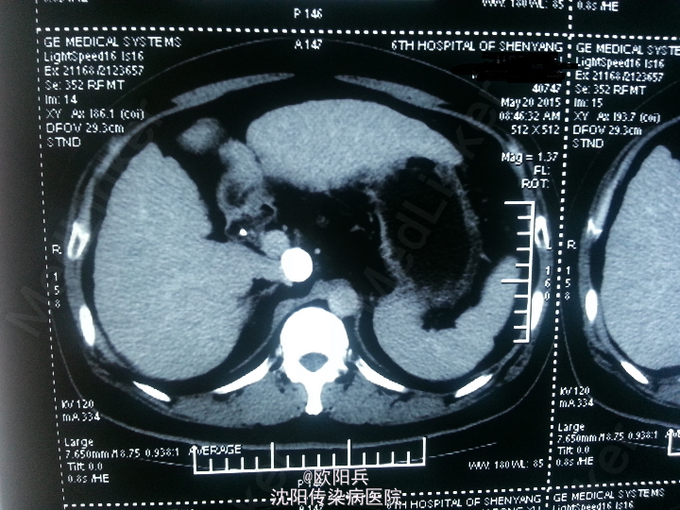

查体:神清语明,面色晦暗,巩膜无黄染,浅表淋巴结无肿大,心肺听诊无异常,腹软,无压痛,肝脾肋下未触及,移动性浊音阴性,肠鸣音正常,双下肢无水肿,扑翼样震颤阴性。 化验:血细胞分析(五分类):*白细胞计数 3.6 10^9/L、*血小板计数 113.0 10^9/L↓、*血红蛋白 166 g/L、中性粒细胞百分比 60.7 %,肝功酶谱:*丙氨酸氨基转移酶 92 U/L↑、*总蛋白 75.0 g/L、*白蛋白 47.0 g/L、*总胆红素 24.0 umol/L↑,糖化血红蛋白检测:糖化血红蛋白 13.50 %↑,*葡萄糖测定:*葡萄糖 15.66 mmol/L↑,血清离子测定:*钾 4.61 mmol/L,肾功能检测:*尿素 5.25 mmol/L、*肌酐 47.3 umol/L↓,血浆氨测定:血氨 29.00 ,凝血五项:凝血酶原时间 9.5 秒↓,乙肝六项:乙型肝炎病毒表面抗原 阳性(+) ↑、乙型肝炎病毒e抗体 阳性(+) ↑、乙型肝炎病毒核心抗体 阳性(+) ↑,丙型肝炎抗体测定(发光法):丙肝抗体 0.01 S/CO,甲胎蛋白测定:甲胎蛋白 7.29 ng/mL。 心电图:正常。 彩超(2015-5-17我院门诊):肝硬化、脾面积大,肝右叶高回声性质待定。 CT:1、肝尾叶占位介入术后改变;2、脾大,肝硬化,肝内多发RN可能性大。

根据患者病史、临床表现及目前辅助检查分析诊断:1、乙肝肝硬化 代偿期 活动性(C-P A级);2、原发性肝癌(肝尾叶)介入术后;3、2型糖尿病。主要诊断依据有: 1、患者乙肝肝硬化、肝癌介入病史明确,2型糖尿病史2年余。2、查体:面色晦暗,移动性浊音(-)。3、化验:患者肝功示转氨酶升高,无低白蛋白血症,C-P评分5分,支持乙肝肝硬化 代偿期 活动性(C-P A级)。糖化血红蛋白 13.50 %↑,葡萄糖 15.66 mmol/L↑,支持2型糖尿病。关于鉴别诊断,患者无酗酒史,不考虑酒精性肝病。其肝癌经DSA下肝动脉造影证实,无需鉴别。患者复查增强CT示肝尾页栓塞密实,边缘无强化,可暂无进一步处理,定期复查。本次住院行常规护肝抗肿瘤治疗。

患者半年前行介入治疗,效果如图,此类患者需密切观察肿瘤进展,目前暂无特殊处理。